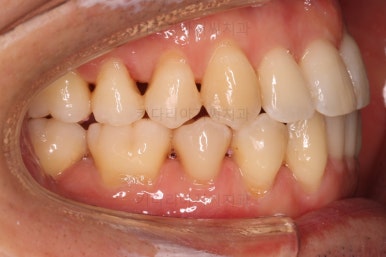

부산비수술교정 키다리아저씨치과에 처음 내원하셨을 당시의 입 안의 모습입니다.

아래 앞니에 결손치아가 하나 있네요. 송곳니-송곳니 사이에 앞니가 4개가 있어야 정상이지만 이 분은 3개에요. 의외로 아래앞니 하나 혹은 두개가 없는 경우가 굉장히 많답니다.

갯수가 맞지 않다보니 치열의 중앙도 맞지 않고 비대칭이 됩니다.

그리고 주걱턱이기 때문에 당연히 아랫니들도 앞으로 나올 수 밖에 없어 윗니보다 앞에 나와있어요.

이를 반대교합이라고 합니다.

어금니의 맞물림도 연쇄적으로 몇 칸씩 밀려있는 양상이라 효율도 좋지 못하고 치아의 건강에도 좋지 못해요.

이 분의 경우에도 전반적으로 잇몸이 약해져있을 수 밖에 없어요. 보시면 아시겠지만 잇몸 퇴축이 심해서 치아들이 길쭉길쭉해 보이죠.